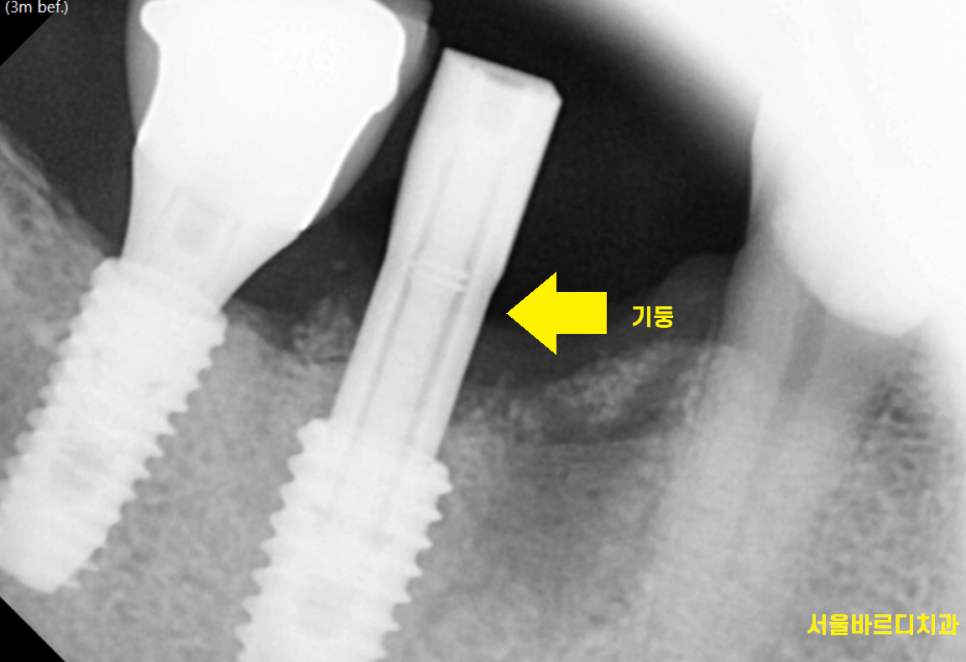

그리고 나서 1달 뒤

임플란트 체크를 위하여 내원하셨는데요.

수치가 너무 잘 나와주었습니다.

일반적으로 80 이상이면 임플란트가

잘 붙었다고 표현하는데

90이 나와주었네요.